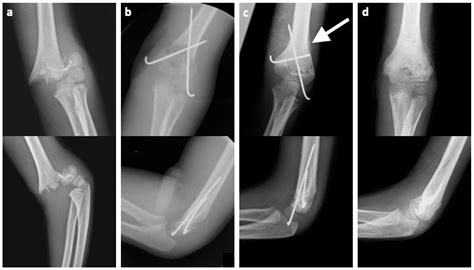

Surgical Treatment

For displaced or completely displaced fractures (Type II and Type III), surgical treatment is often required to realign the bone fragments and stabilize the fracture. Common surgical procedures include:

• Closed reduction and percutaneous pinning (CRPP): This procedure involves manipulating the bone fragments back into place without open surgery and then inserting pins to hold them in position.

• Open reduction and internal fixation (ORIF): In more severe cases, open surgery may be necessary to realign the bone fragments and secure them with plates, screws, or other hardware.

Surgical treatment aims to restore the normal anatomy of the elbow and promote healing. Post-operative care typically includes immobilization, pain management, and physical therapy to regain range of motion and strength.

Supracondylar humerus fractures are classified based on the direction of the fracture line and the displacement of the bone fragments. The most commonly used classification system is the Gartland classification, which includes three types:

Type II Displaced fracture with posterior angulation of the distal fragment

Type III Completely displaced fracture with no cortical contact between the fragments

Understanding the classification of the fracture is essential for determining the appropriate treatment plan.